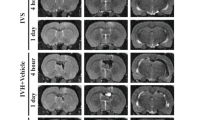

Seven PK studies were performed on four patients. Their therapy and QA values are listed in Table 1.The CSF EPO concentrations reflected the serum EPO levels and the permeability of the BBB (Fig.1A). The concentration of EPO in the CSF increased in all four patients after 1–3 h, peaked after approximately 24 h and declined bi-exponentially thereafter with similar terminal slopes in serum and CSF (Table 2). The serum and CSF EPO concentration-time profiles after administration of three EPO doses reflected the IV dosing schedule (Fig.1B). The EPO concentration in CSF peaked 4–10 h after each dose.

A Predicted (solid line) and observed concentrations of erythropoietin (EPO) in serum (circles) or cerebrospinal fluid (CSF) (triangles) in patient 1 who received a single 667 IU/kg (open symbols) and 1,500 IU/kg (closed symbols) IV doses and in patients 2, 3 and 4 who received a single 1,500 IU/kg IV dose of Eprex. B Predicted (solid line) and observed concentrations of EPO in serum (circles) or CSF (triangles) in patient 2 who received three 500 IU/kg (40,000 IU) Eprex doses every 24 h and in patient 4 who received three 667 IU/kg (40,000 IU) Eprex doses every 24 h

For patient 2, CSF samples were obtained from the Ommaya reservoir and by lumbar puncture (LP) 24 h after the third dose of EPO. The CSF sample obtained by LP showed increased cell numbers and 24-fold higher concentrations of EPO and albumin than the Ommaya reservoir derived sample (Table 3). The QA of the LP sample was elevated to 0.09860 (normal range±2SD=0.0018−0.0074) consistent with a localized increase in BBB permeability [17]. Thus, the increased EPO concentration in the LP sample appeared to reflect the concentration gradient of albumin. Magnetic resonance imaging scans demonstrated leptomeningeal enhancement over the conus and lumbar roots but no leptomeningeal or parenchymal brain metastases.

Compartmental and non-compartmental analyses identified the serum concentration of EPO and the QA as the two principal determinants for the EPO concentration-time profile in the CSF. Using these two variables, we constructed a PK model with the assumptions described in the methods (Fig.2A). The estimated parameters for the PK model are listed in Fig.2B. The predicted concentration-time profiles of EPO in serum and CSF are based on the estimated model parameters and are shown as the solid lines in Fig.1A. For patient 1, the predicted concentration-time profiles in serum and CSF for the lower IV dose of 667 IU/kg are based on the model parameters estimated from the higher IV dose of 1,500 IU/kg in the same patient. There was a close agreement between the predicted profiles and observed data, suggesting that this PK model accurately describes the disposition kinetics of EPO in serum and CSF.

The distribution of EPO into the CSF followed first-order kinetics, with serum concentration as the driving force, and depended on the permeability of the BBB as measured by the CSF/albumin ratio (QA). A PK model using these assumptions was able to describe the concentration-time profiles of EPO in the CSF. The predictive value of the model can be illustrated by simulations predicting how certain dosing regimens (such as an initial 1,500 IU/kg IV dose followed by two daily 500 IU/kg IV doses) can be used to rapidly increase and then maintain the concentration of EPO in CSF (Fig.3).

Predicted concentration-time profiles of erythropoietin (EPO) in serum (upper line) and in cerebrospinal fluid (CSF) (lower line) after a single 1,500 IU/kg IV dose (left panel), three daily 500-IU/kg IV doses (middle panel), and a single 1,500 IU/kg IV dose on day 1 followed by two daily 500-IU/kg IV doses on day 2 and day 3 (right panel). Single-dose PK parameters for patient 2 and a QA value of 0.00406 were used in the simulations